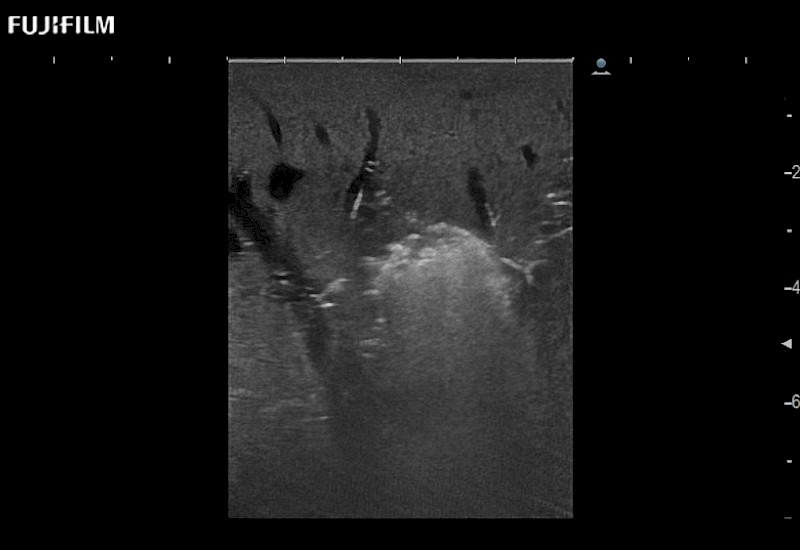

Learn moreFujifilm Healthcare continues to listen to the experts, our neurosurgeons, by developing an ultrasound system specifically designed for the Operating Room.

Guidance is the fundamental purpose for all of our surgical ultrasound technology. Fujifilm Healthcare is committed to designing tools that help neurosurgeons navigate inside the human body and provide the necessary information to immediately make critical surgical decisions.

With the ARIETTA Precision the next level of surgical ultrasound is here.